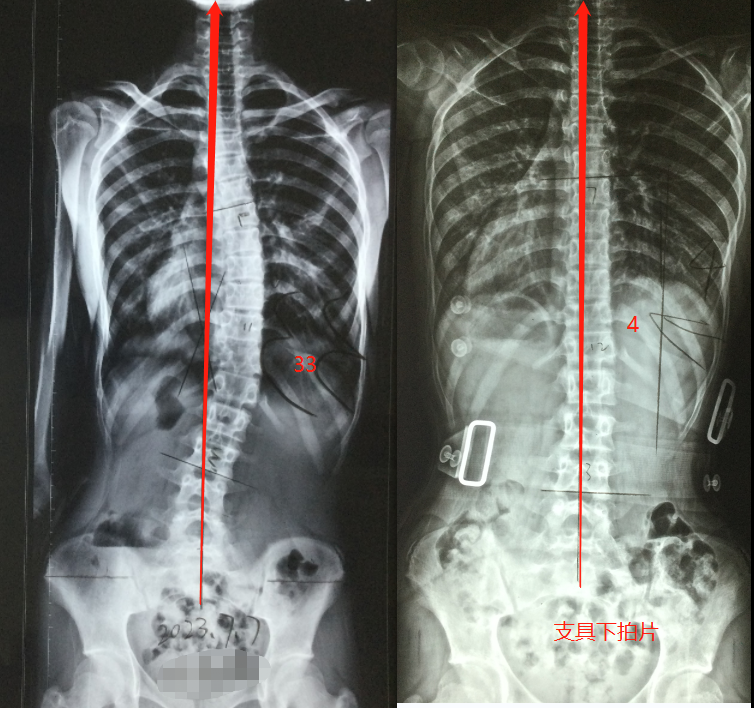

脊柱侧弯超过30°,怎么才能恢复的快?医生用一篇案例告诉您

图片尺寸754x708